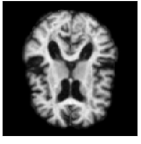

Figure 3: 4 time steps of a sample of the stochastic deformation process I0ϕt1subscript𝐼0superscriptsubscriptitalic-ϕ𝑡1I_{0}\circ\phi_{t}^{-1} at t=0, 0.25, 0.5, 1𝑡00.250.51t=0,\,0.25,\,0.5,\,1.

By drawing sample paths of the stochastic flow ϕt1superscriptsubscriptitalic-ϕ𝑡1\phi_{t}^{-1}, we obtain samples of deformed images under the model. Sample images at t=1𝑡1t=1 are shown in Fig. 2, together with a plot of the generated image variation, and the noise fields used to simulate the sample data. Fig. 3 shows 4 time points from a sample path of the stochastic process I0ϕt1subscript𝐼0superscriptsubscriptitalic-ϕ𝑡1I_{0}\circ\phi_{t}^{-1} for t=0, 0.25, 0.5, 1𝑡00.250.51t=0,\,0.25,\,0.5,\,1.